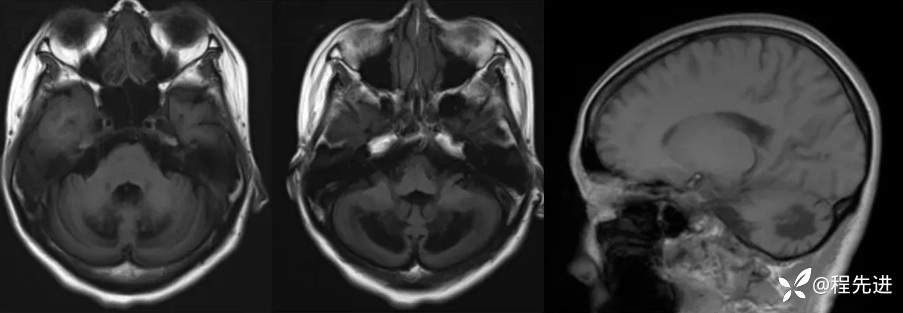

T1:

T2、FLAIR:

颅脑MRI增强: